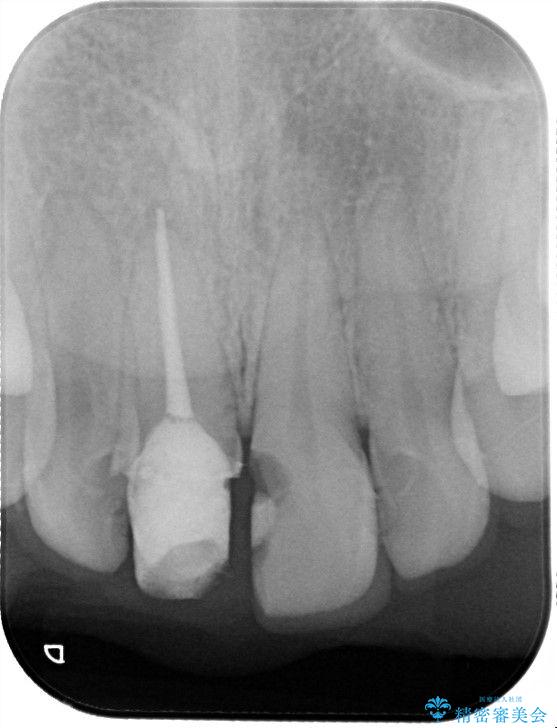

- 他院で治療した前歯の色が気になるということで来院された患者様です。前歯に色の差があり、レントゲンから内部にう蝕も見られたため、審美性に優れ、う蝕になりにくいオールセラミッククラウンで治療いたしました。